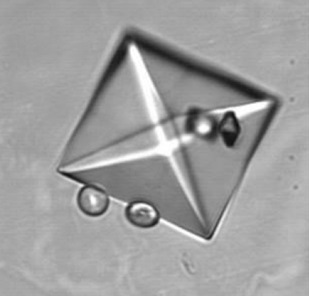

신장 결석은 주로 칼슘염으로 구성되며, 옥살산칼슘(70-80%)이 가장 흔하고, 인산칼슘과 요산이 그 뒤를 잇는다. 신장 결석 형성은 다음 세 단계를 거친다.[22]

# 핵 생성 (초기 결정 형성)

# 성장 (단일 결정의 확장)

# 응집 (여러 결정의 덩어리 형성)

소변이 과포화 상태일 때, 즉 소변 용매가 용질을 용액 상태로 유지할 수 있는 양보다 더 많은 용질을 포함할 때, 하나 이상의 결석 생성 물질이 핵을 통해 초기 종자 결정을 형성할 수 있다. 이질 핵 생성은 동질 핵 생성보다 더 적은 에너지가 필요하기 때문에 더 빠르게 진행된다. 신장 유두 표면의 세포에 부착된 종자 결정은 성장하여 조직화된 덩어리로 응집될 수 있다. 소변 pH가 비정상적으로 높거나 낮을 때 결석 형성 과정이 더 빠르게 진행될 수 있다.

결석 생성 화합물에 대한 소변의 과포화는 pH에 따라 달라진다. 예를 들어, pH 7.0에서 소변 내 요산의 용해도는 158 mg/100 mL이지만, pH를 5.0으로 낮추면 요산의 용해도가 8 mg/100 mL 미만으로 감소한다. 소변의 과포화는 요산과 시스틴 결석의 주요 원인이지만, 칼슘 기반 결석은 더 복잡한 원인을 가질 수 있다.